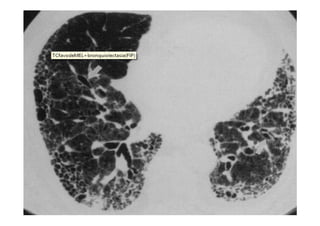

Radiografia e TC de tórax

Utiliza-se com frequênciap/ avaliar: O posicionamento do TOT: 4-6 cm acima da carina; Se os pulmões estão sendo aerados adequadamente; Alterações patológicas e diagnóstico de pneumopatias; Outros. Radiografia e TC de tórax